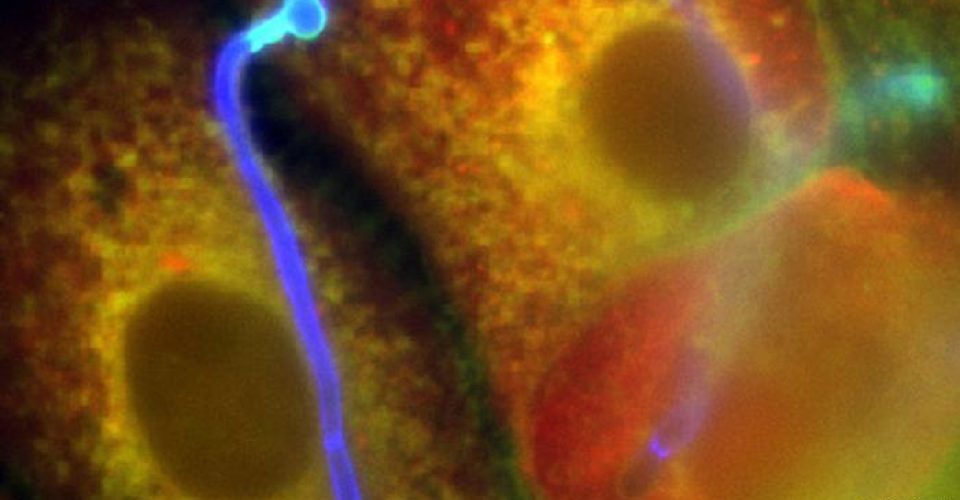

Os fungos atacam sobretudo as superfícies corporais, não só a pele externa, mas também as internas, que entrem em contato com o ar. Aspirados, seus esporos se instalam nos sinos nasais, indo daí para as vias pulmonares mais profundas, ou, se atravessam as mucosas, até os ossos.

Além disso, no diabetes não tratado, as mucosas produzem moléculas que agem como receptores para o mucor. “Ele pode então se fixar nelas. Aí começa imediatamente a crescer, e os esporos se transformam num fungo em forma de fio”, descreve Cornely.